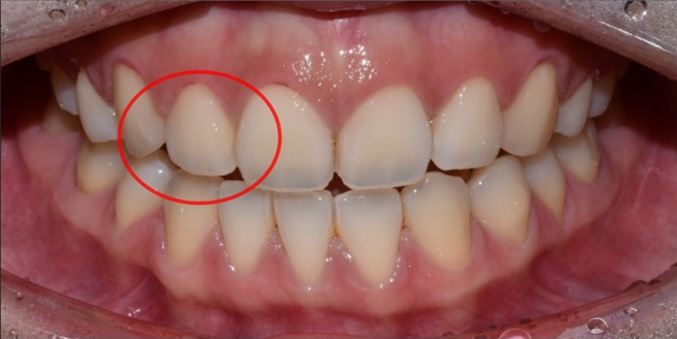

여러분이 고민하시는 작은 이빨은 왜소치(microdontia)라고 해서 기존 정상 치아보다 크기가 작은 치아를 말합니다.

대체로 측절치(두 번째 앞니, 대문니 양옆 치아)가 정상 크기보다 작은 경우가 많은데요.

다양한 왜소치 사례

대문니의 약 70~80% 정도의 비율이 측절치의 정상적인 크기라고 한다면, 이보다 훨씬 더 작은 왜소치로 형성되는 것이죠.

물론 치아 자체가 작은 경우도 있지만,

잇몸이 과도하게 내려와서 치아를 덮고 있는 경우에도 치아가 짧아 보이면서 왜소치처럼 보일 수 있습니다.